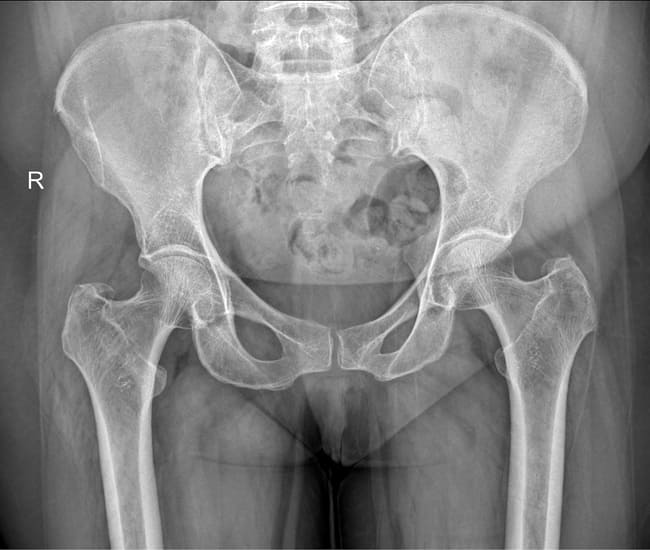

Rontgen pelvis atau rontgen panggul digunakan utamanya pada evaluasi kasus trauma panggul, deteksi fraktur pelvis, dislokasi sendi panggul, serta penilaian osteoarthritis, tumor, dan kondisi inflamasi seperti ankylosing spondylitis. Secara garis besar, rontgen pelvis digunakan untuk menilai struktur tulang dan jaringan lunak di area panggul, termasuk tulang iliaka, ischium, pubis, sakrum, dan sendi-sendi pelvis.[1,2]

Rontgen pelvis umumnya dilakukan pada posisi supinasi. Pada posisi supinasi, proyeksi anteroposterior (AP) adalah proyeksi yang paling umum digunakan. Namun, pada beberapa kasus tertentu, posisi lain seperti posisi berdiri juga dapat dilakukan.[1]

Pada pasien trauma tumpul dengan hemodinamik tidak stabil, rontgen pelvis dilakukan sebagai alat bantu penegakan diagnosis. Dari pemeriksaan rontgen pelvis proyeksi anteroposterior, dapat ditemukan diastasis simfisis pubis, fraktur rami pubik superior dan inferior, dan fraktur avulsi prosesus transversus lumbar kelima.

Proyeksi lain adalah proyeksi outlet, yang didapatkan dengan mengarahkan sumber sinar X miring dari arah kaki pasien dengan sudut 35° terhadap meja periksa. Posisi ini bisa menunjukkan fraktur sakral dan dislokasi kraniokaudal dengan lebih baik. Di sisi lain, posisi inlet (kemiringan 35° dari posisi kepala pasien terhadap meja periksa) memungkinkan deteksi pergeseran sendi sakroiliaka anteroposterior atau rotasi hemipelvis dengan lebih baik.[4]